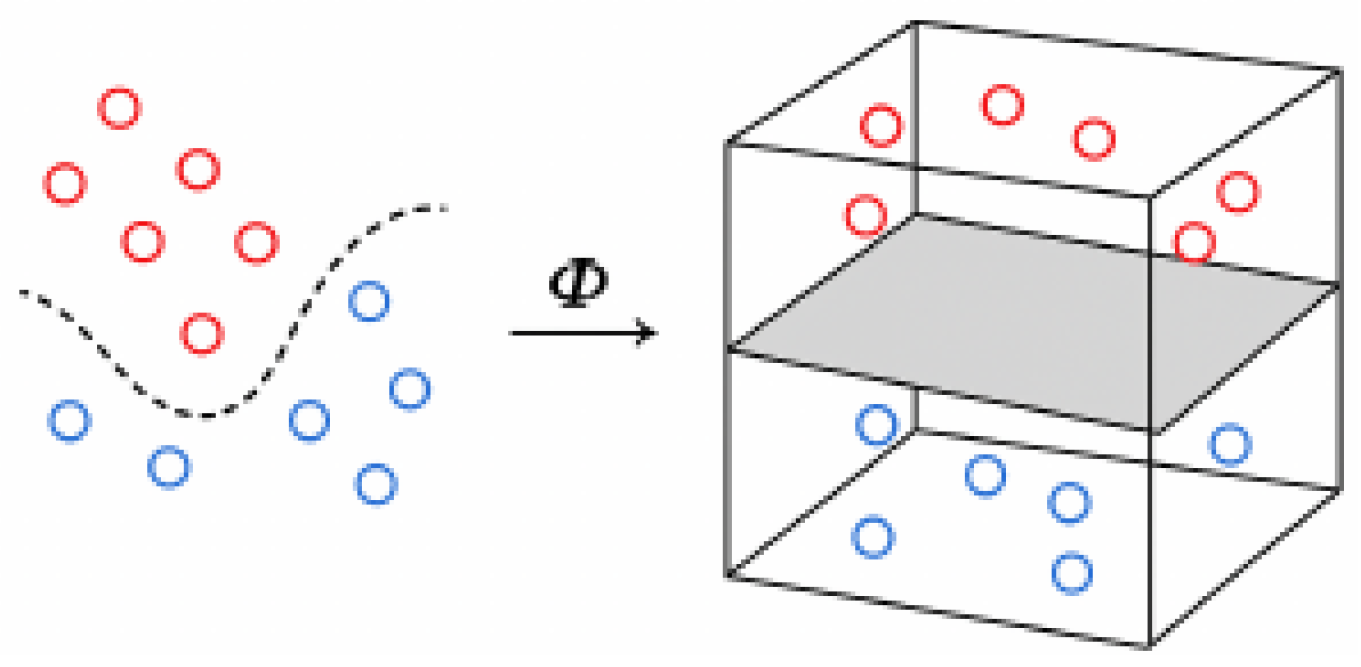

1.2. Support Vector Machine